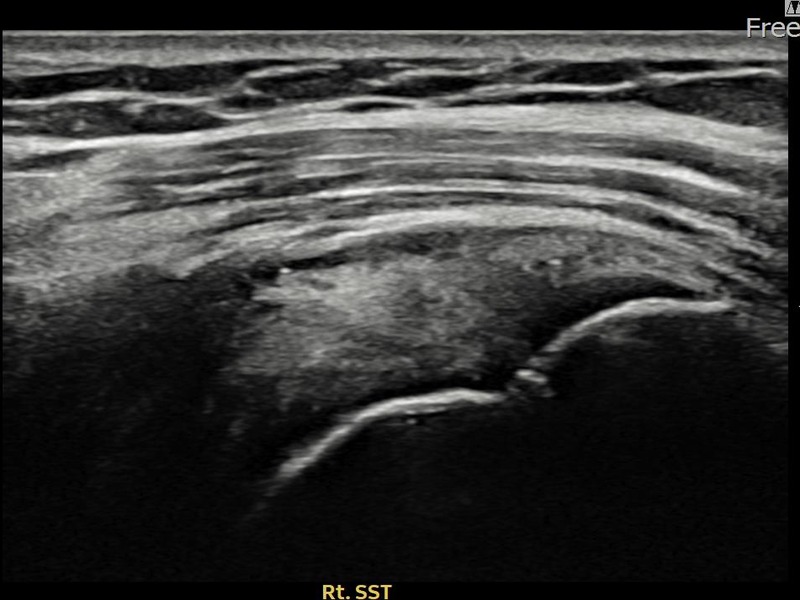

최ㅇㅇ님 · 우측 극상근건 관절면측 파열 진행형

우측 어깨 파열이 진행된 상태로 수술 없이 치료를 원해 내원하셨습니다. 다각도 초음파 평가 후 축소봉합술을 시행하여 힘줄 구조가 안정화되었습니다.

상세 보기 →